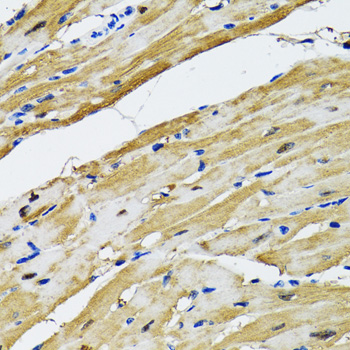

Immunohistochemistry of paraffin-embedded rat heart using GOT1 antibody at dilution of 1:100 (40x lens).